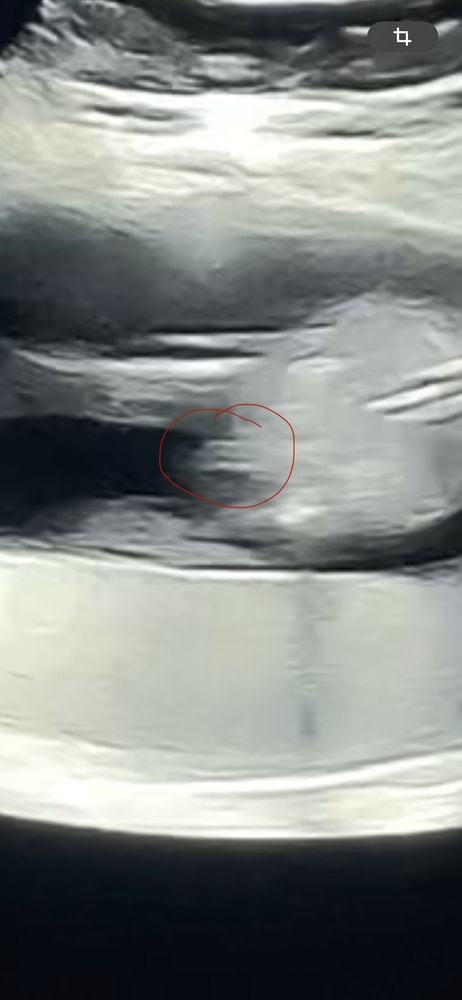

Всем привет, девочки)! Я никак не могу успокоится.. В предыдущем посте рассказала, что у врача возникли сомнения в определении пола на сроке 15 недель и 5 дней. Хотя, увидев снимок с УЗИ, для меня все стало очевидно и я была уверена в мальчике. Но смущают сомнения врача из за которых я отменила гендер пати и девочки на форумах многие пишут, что похоже на девочку. Я пересмотрела короткое видео с УЗИ, которое успела снять. Наделала скрины. Посмотрите кому не лень, на кого больше похоже? Может у вас есть похожие фото? Кто оказался? На повторное УЗИ в другую клинику записалась через неделю, но мысли продолжают одолевать 😅

Натали, вот в каких то моментах и правда буду зернышко, а в каких-то прям очевидный писюн😂 Ох уж этот малыш) С первым ребенком на этом сроке все было понятно и очевидно